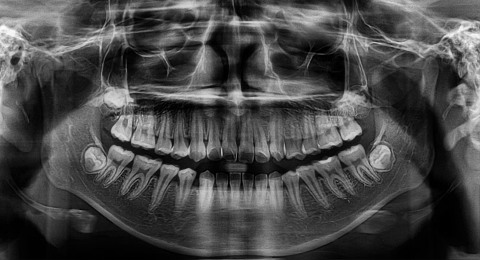

Hình ảnh của Panorex x-quang

Nguy cơ phát triển u màng não thậm chí còn cao hơn trong số những người tham gia khảo sát có báo cáo đã chụp phim panorex (phim toàn cảnh): có chỉ định x-quang panorex định kỳ hàng năm hoặc thường xuyên hơn thì tăng nguy cơ bị gần 3 lần và nếu ở trong độ tuổi dưới 10 thì khảng năng nguy cơ cao 4,9 lần so với nhóm đối chứng. Phim panorex là một X-quang cho thấy toàn cảnh hàm trên và dưới cũng như các răng trong cùng một phim.